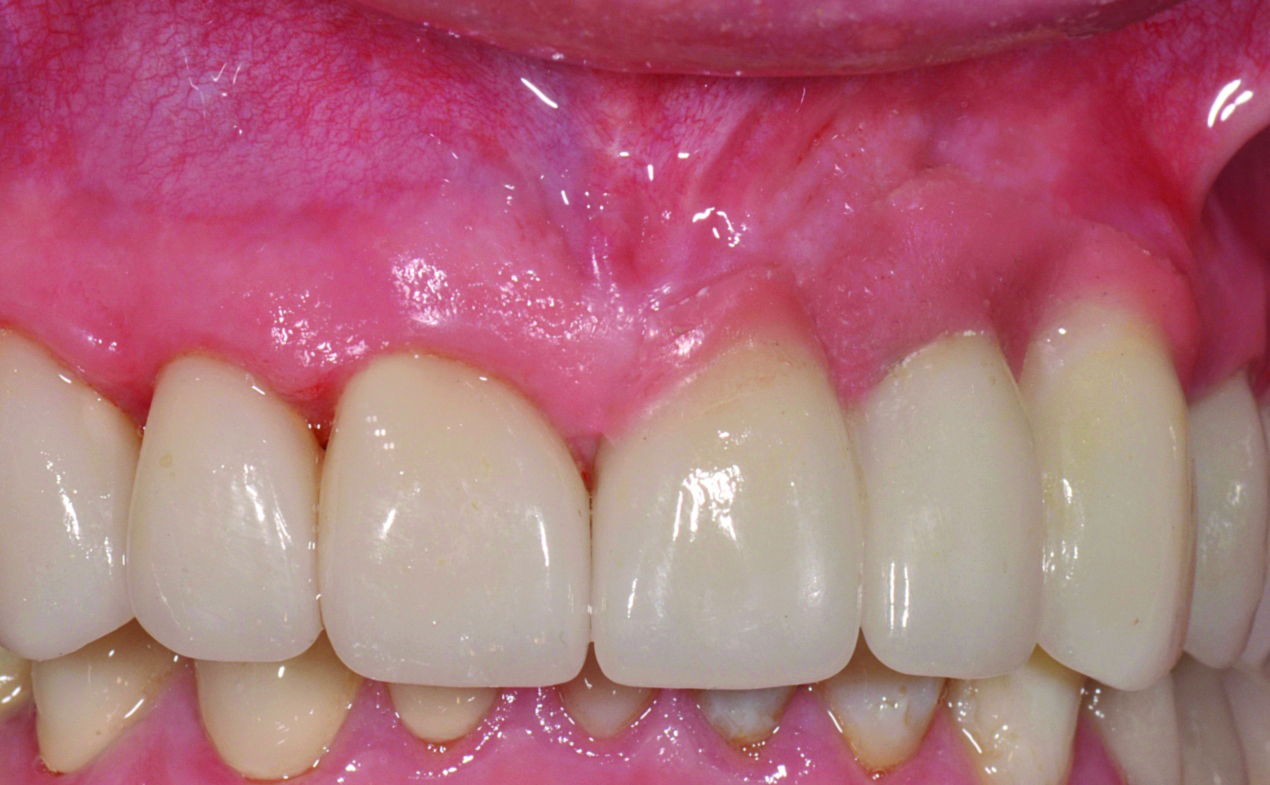

Fig 30. Postoperative clinical view, which illustrates good tissue contours interproximally and on the facial of the implants.

Figure 30

In the final case, adjacent implants were placed in healed sites No. 8 and No. 9 and provisionalized at the time of surgery (Figure 27 and Figure 28). This case illustrates the effect of platform switching on bone and gingival tissue stability, as well as recognizing that appropriate diameter and spacing is important to maintain ideal ridge contour. The gingival tissue anatomy between implants is characteristically shorter than papilla form between adjacent teeth, and, as a consequence, it is important to incorporate implant designs and procedures that minimize bone-level changes and associated soft-tissue recession. The depth of implant placement was subcrestal relative to the ridge crest, based on the future desired free gingival tissue level, while allowing prosthetic running room. The studies of Barros et al and Veis et al noted that implants positioned subcrestally (as seen in Figure 29) showed better crestal bone preservation than those placed equicrestally or supracrestally.28,29 The implant design used in this case achieves excellent primary stability. Along with the optimal 3-dimensional positioning of the implants and, specifically, the subcrestal placement, as well as the immediate provisionalization protocol, these concepts and implants have contributed to a pleasing esthetic outcome, as seen in Figure 30.